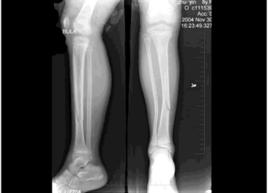

骨折後,因骨折本身及鄰近組織的血管斷裂、出血,在骨折部形成血腫,血腫於傷後6~8小時開始凝結成含有網狀纖維素的血凝塊。骨折斷端因損傷及血循環中斷,致部分骨細胞壞死,24小時內新生的毛細血管、成纖維細胞和吞噬細胞侵入血塊,一方面血腫被機化,另一方面纖維組織將血凝塊分隔為許多小塊,同時壞死組織被吞噬細胞清除。此後,吞噬細胞和毛細血管逐漸減少,被機化的血腫和肉芽組織再演變成纖維結締組織,使兩斷端初步連線在一起,此時纖維癒合,約在骨折後2~3周內完成。在此期內,尚可再次整復,以調整外固定或牽引方向,從而矯正斷端的對位及對線不良。